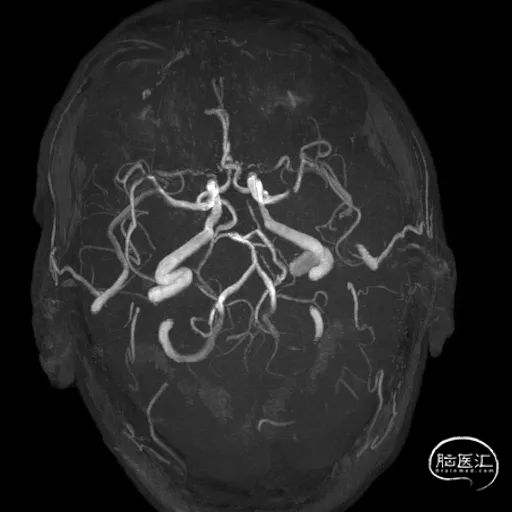

术前影像学检查结果

术中3D证实明确左侧大脑中动脉重度狭窄,完成测量并选取治疗角度。